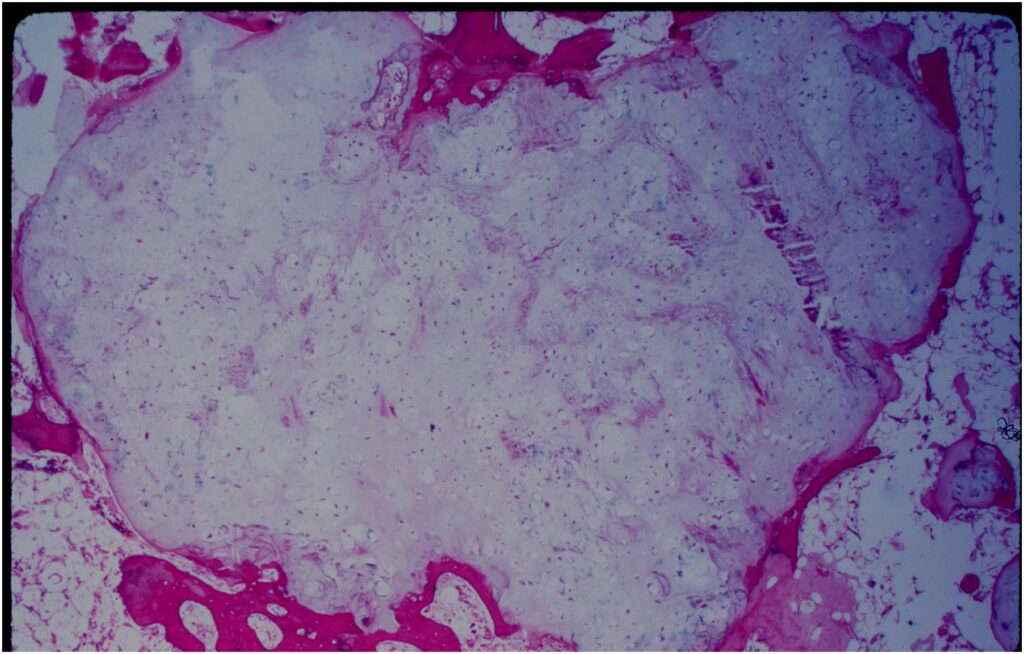

- Rests of hyaline cartilage with a lobular growth pattern

- Cells are within lacunae

- Hypocellular with cells spaced apart separated by matrix

- Cells have small nuclei and are similar size and shape (no pleomorphism)

- No mitotic figures

- The matrix has a ground glass basophilic appearance

- Hyaline cartilage often with myxoid areas

- Variable amorphous calcification and enchondral ossification

- May cause mild expansile remodeling of bone and cortical thinning

- Enchondromas are well defined lesions with cartilage arranged in lobules that are separated by fibrovascular septa